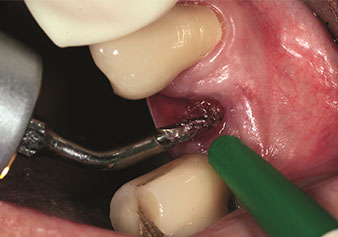

Eine oft unterschätzte Anwendung ist die schonende Extraktion von Zahnwurzeln oder auch von Wurzelfragmenten im Rahmen des Alveolenmanagements. Mit den feinen Periotomen, die aktuell in zwei Ausführungen (EX1 und EX2 von W&H) zur Verfügung stehen, lassen sich auch speziell endodontologisch vorbehandelte Zähne oder ankylosierte Wurzeln mühelos entfernen. Das Ergebnis sind Extraktionsalveolen, deren Hart- und Weichgewebe völlig intakt sind, da in der Regel auf ein Aufklappen verzichtet werden kann.

Dies stellt anschließend eine optimale Basis für eine spätere oder Sofortversorgung mit Implantaten dar (Abbildung eins und zwei mit freundlicher Genehmigung von Dr. Torsten Conrad, Bingen a. Rhein).

Feines Periotome (Instrument EX1)

Abb. 1: Feines Periotome (Instrument EX1).

Foto: © Dr Torsten Conrad (Bingen a. Rhein)